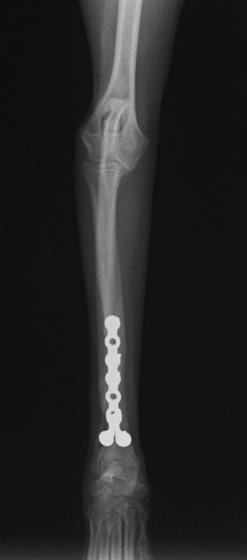

トイプードル 右遠位橈尺骨短斜骨折のALPSによる内固定

Locking Compression Plate

LCPは、スクリュー(ネジ)とプレート(金属の板)をロックする特殊な構造により骨折部位を固定する新しい世代のプレートシステムです。ひとつのホールでロッキングスクリューとスタンダードスクリューの使用を選択できるユニークな構造をしているため、骨折断端間の圧迫を目的とした従来型プレート固定法に加え、高い角度安定性を有するロッキングスクリューを用いた固定法の選択が可能です。従来のプレートシステムでは困難だった部分の骨折や癒合不全の症例に高い治療効果をもたらします。